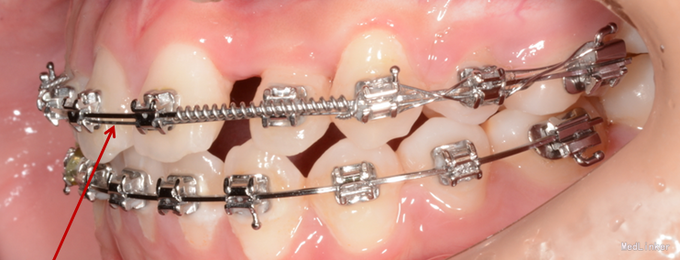

诊断:先天缺牙;22牙埋伏阻生 治疗:排齐整平后,拔除乳侧切牙(先保留乳牙不拔的目的是为了保持骨量)然后开窗牵引恒2,先用弹力线逐渐加力,牙齿快移入牙弓的时候粘接拖槽,用12niti的辅弓辅助22牙排齐,同时主弓丝仍为1825ss维持弓形不变。

目前此患者已进入精细调整阶段,效果不错。对阻生牙的牵引一般都要求在硬丝上才行,以免将弓形拉塌陷,后期快拉到位的时候,辅弓是个很好的选择,能快速排齐牵引的牙齿,同时主弓丝又能维持弓形的完整。